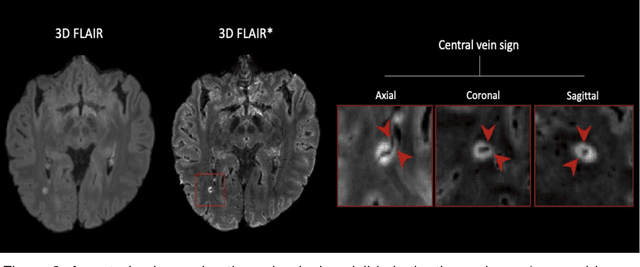

Abstract:The current multiple sclerosis (MS) diagnostic criteria lack specificity, and this may lead to misdiagnosis, which remains an issue in present-day clinical practice. In addition, conventional biomarkers only moderately correlate with MS disease progression. Recently, advanced MS lesional imaging biomarkers such as cortical lesions (CL), the central vein sign (CVS), and paramagnetic rim lesions (PRL), visible in specialized magnetic resonance imaging (MRI) sequences, have shown higher specificity in differential diagnosis. Moreover, studies have shown that CL and PRL are potential prognostic biomarkers, the former correlating with cognitive impairments and the latter with early disability progression. As machine learning-based methods have achieved extraordinary performance in the assessment of conventional imaging biomarkers, such as white matter lesion segmentation, several automated or semi-automated methods have been proposed for CL, CVS, and PRL as well. In the present review, we first introduce these advanced MS imaging biomarkers and their imaging methods. Subsequently, we describe the corresponding machine learning-based methods that were used to tackle these clinical questions, putting them into context with respect to the challenges they are still facing, including non-standardized MRI protocols, limited datasets, and moderate inter-rater variability. We conclude by presenting the current limitations that prevent their broader deployment and suggesting future research directions.